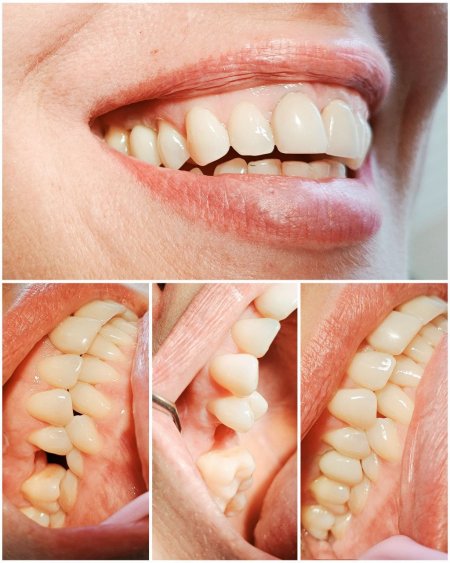

Сучасна стоматологія дозволяє відновити втрачені зуби настільки природно, що відрізнити імплант від власного зуба практично неможливо. Саме тому дедалі більше кременчужан обирають цей метод лікування.

Як підібрати імпланти правильно? Стоматологи радять звертати увагу на якість матеріалів, гарантії виробника та досвід лікаря. Від цього залежить не лише комфорт, а й довговічність результату.

Клініка «Мрія» у Кременчуці працює за перевіреними методиками, які дозволяють відновити усмішку всього за 7 діб — навіть у випадках повної відсутності зубів. Лікарі обирають рішення індивідуально, щоб кожен пацієнт отримав стабільний і передбачуваний результат.

Важливою перевагою є співпраця з мережею клінік «Кринички» у Києві. Це партнерство забезпечує обмін досвідом і впровадження сучасних протоколів, завдяки чому кременчужани отримують стоматологічні послуги на рівні столичних центрів.

Клініка «Мрія» поєднує досвід лікарів, сучасні технології та уважне ставлення до кожного пацієнта. Тут переконані: здорова усмішка змінює якість життя, додає впевненості та дарує гарний настрій щодня.